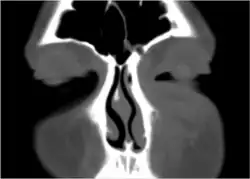

If the diagnosis is unclear, a CT scan may be done to rule out other possibilities.

Periorbital cellulitis caused by a dental infection (also causing maxillary sinusitis) -